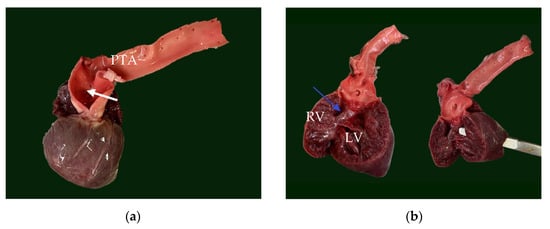

The heart was significantly enlarged (organ weighed 37 g, representing 1.12% of total body weight) with prominently thickened, ventricular walls (bilateral ventricular hypertrophy). Originating from the base of the heart, a single large arterial trunk (PTA) (measuring 0.8 cm) with its ventricular outflow tract was observed (Figure 4). At 0.5 cm from its origin, the PTA gave rise to the pulmonary artery, which subsequently branched into the right and left pulmonary arteries. Under the arterial trunk, within the upper segment of the interventricular septum a large and non-restrictive septal defect measuring 1.2 cm was observed. Due to all the identified features, the single large arterial trunk was identified as a persistent truncus arteriosus type 1 (Figure 5a,b).

Figure 5.

(a) Truncus arteriosus with the opening of pulmonary artery (white arrow). (b) The septal defect (blue arrow) which created direct communication between the two ventricles through the septal defect; the scissor could transverse directly from left ventricle to right ventricle. (c) Exterior aspect of the left atrial diverticulum (blue arrow) which originated from the left atrium. (d) The gross aspect of the abnormal fibrous membrane (blue arrow) adherent to lung pleura. PTA—persistent truncus arteriosus, RV—right ventricle, LV—left ventricle.